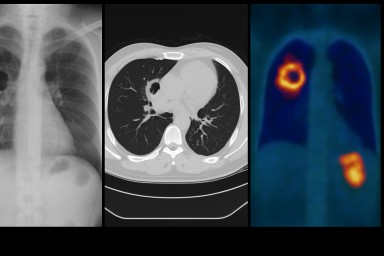

Understanding Aspergillosis Through Imaging: A Guide for Patients and Non-Specialist Clinicians

Imaging — especially chest X-ray and high-resolution CT (HRCT) — is one of the most important tools for recognising, diagnosing and monitoring aspergillosis. Because the condition can affect the lungs in very different ways, seeing what is happening inside the chest is essential for both patients and clinicians.

This guide explains why imaging matters, how it is used, and provides links to trusted resources that show what aspergillosis looks like on scans.